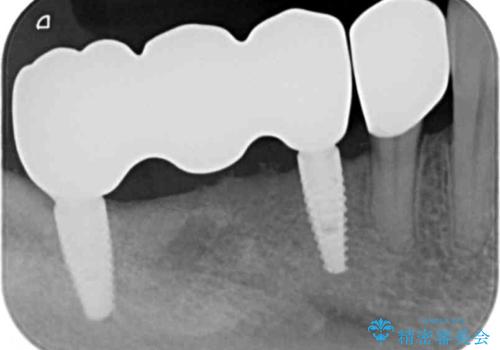

- 275万円(インプラント×5・チタンカスタムアバットメント×5・ジルコニアクラウン×7・仮歯×7)費用は治療当時の料金となります

奥歯を多数失い全く噛めない期間があり、困り果てて来院されましたが、インプラント治療をおこなったことでしっかりと噛めることができるようになりまた食事を楽しめるようになったと大変喜んでいただくことができました。